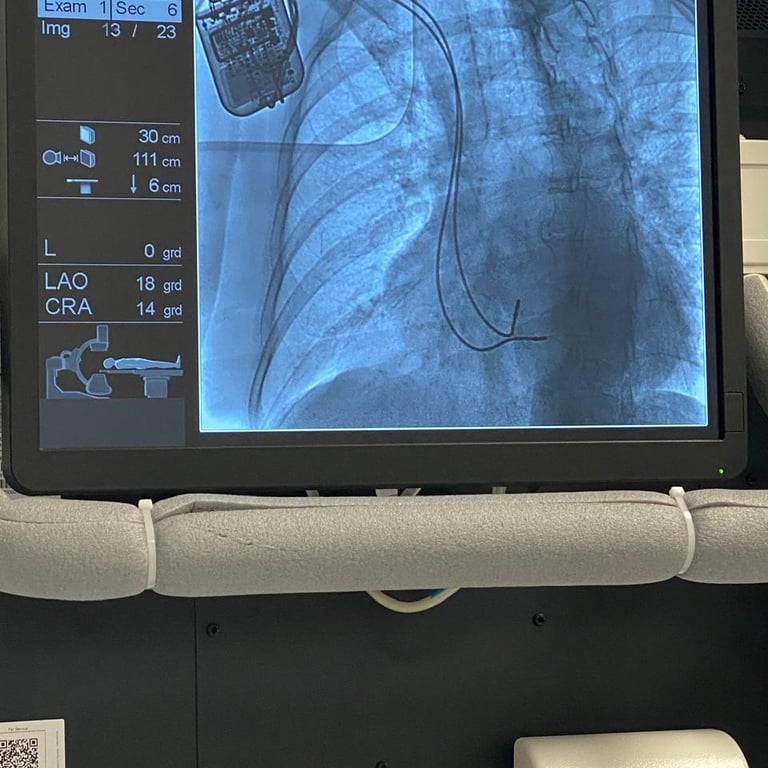

El 2 de Enero del 2024 se realizó el segundo implante de la terapia de modulación de la contractilidad cardiaca a cargo del Doctor Ulises Rojel Martínez en la Ciudad de Puebla